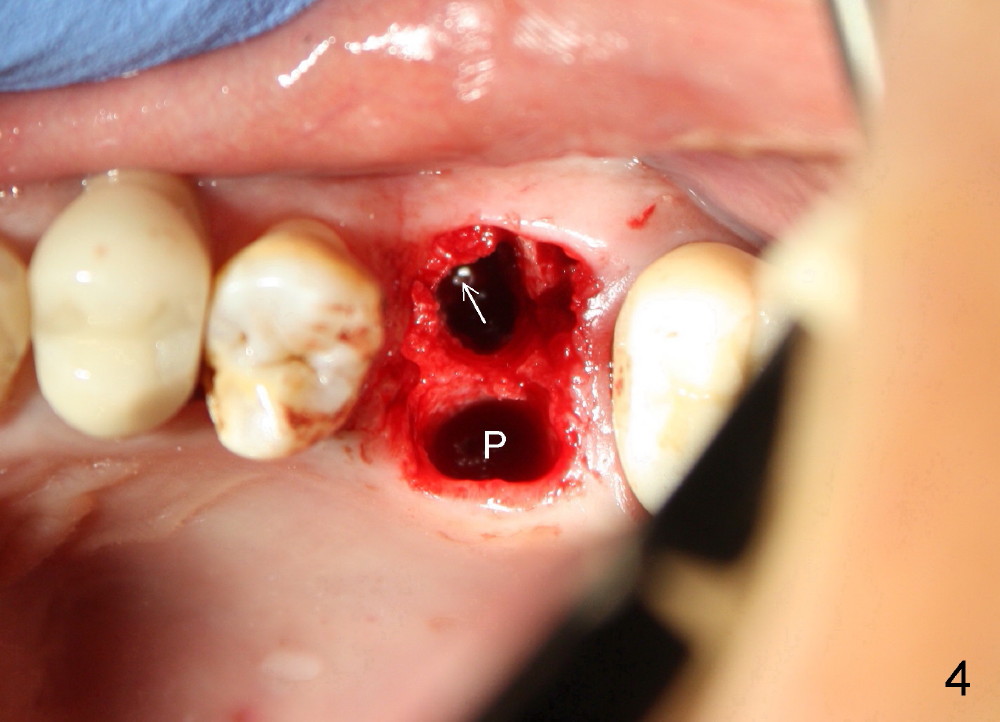

The upper left 1st molar is extracted with sectioning. The septum is large. A surgical fissure bur is used to initiate an osteotomy in the middle of the septum (Fig.1 <; P: palatal socket, MB: mesiobuccal socket), followed by tapping with resistance a 2 mm osteotome ~ 8 mm into the septum. It is tougher to drive 3 mm osteotomy. A 2.5 mm reamer is used to enlarge the osteotomy at 50 RPM at the same depth. Then it is relatively easy to tap 3 and 4 mm osteotomes at ~ 8 mm into the septum. A 4.5x17 mm tap is inserted 8 mm deep with binding to the septum. PA is taken (Fig.2). It appears that the sinus floor (black >) has been penetrated, but the osteotomy has not reached the apex (white >) of the palatal (P) socket. Then the tap is advanced ~ another 3 mm. When the tap is removed, the osteotomy (Fig.3 O) is slightly toward the buccal aspect of the extraction socket, but it has intact wall, including the mesiobuccal (>). The apex of the ostoetomy has no bone, but there is no air leakage. The next tap, 5x17 mm, is inserted shallower (~ 8 mm in the septum; to reduce potential trauma) with stability. However, 6x17 mm tap at the same depth does not obtain stability, since the osteotomy deviates severely mesiobuccally (Fig.4 arrow) with breakdown of the mesiobuccal wall. So the osteotomy has to be deeper in order to achieve stability of 6x17 mm tap (by engaging into more apical bone). A 7x17 mm tap is then intended to be inserted to close the socket as much as possible, but as it is being inserted, the osteotomy is more severely deviated and tilted mesiobuccally with the original mesiobuccal wall further being broken down (not shown). It appears to compromise stability. Mixture of autogenous bone from reamer, allograft and synthetic bone is placed in the mesiobuccal and palatal sockets before placement of the 6x17 mm implant (Fig.5 I). Unfortunately some of graft blocks the apical osteotomy. To clear the blockage, some of previous osteotome and taps are re-inserted. The result is in fact beneficial, as bone graft (G) is pushed upward. Prior to implant placement, nose blowing test does not produce air leakage. More allograft is placed in the coronal portion of the sockets (Fig.6 G); an abutment with precut slots is placed (A) with intention of better holding perio dressing in place after placement of a collagen dressing (Fig.7 M). A temporary crown may be placed when the perio dressing is dislodged. The provisional is to keep the membrane and bone graft in place. The patient returns for follow up 1 week postop. He is symptom free. The abscess appears to be resolving (Fig.8 >); the perio dressing remains in place.